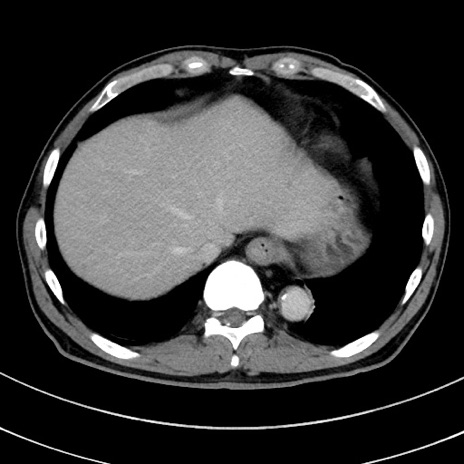

症例8(横断像)

【症例】 60歳代男性

【主訴】 黒色吐物

【現病歴】 4日前から嘔気自覚、2日前の朝食後にも嘔気あり、自分で手で嘔吐反射起こし嘔吐したところ血が混ざっていたため受診。

【既往歴】 5年前汎発性腹膜炎を伴う急性虫垂炎で手術、高血圧、前立腺肥大症、高脂血症

【身体所見】 腹部正中に手術癩痕あり 腹部平坦・軟圧痛なし膨満感あり

【データ】WBC 8400、CRP 4.54